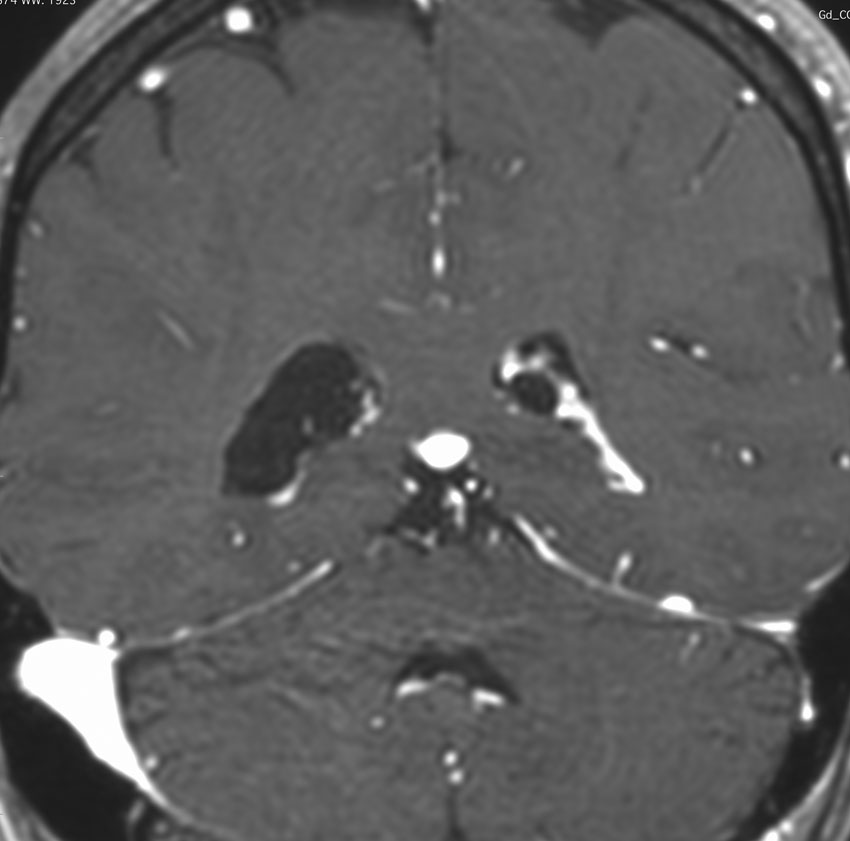

側頭部脈絡裂のう胞 temporal choroidal fissure cyst

内側側頭葉の側脳室側頭角の内側にできる小さなのう胞です。よくみるもので何もしないで放置します。通常は無症状ですが,とても大きくなると側頭葉てんかんを生じることがあります。組織は,choridal cyst, arachnoid cyst, glial cystなどと報告されています。

左側の画像は例外的に大きなものです。通常は10-20mmくらいの小さな丸いのう胞として見られます。